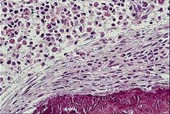

Ved beinaffeksjon utvikler 60 – 70 % radiologisk påvisbare lesjoner. Skjelettforandringene kan være forårsaket av mediatorsubstanser (13). Beinmargen er det hyppigst affiserte organ, bortsett fra hud. Det sees to forskjellige former av mastcelleinfiltrasjon: fokale mastcelleaggregater eller mer diffust utbredte mastcelleinfiltrater, ofte med økt granulopoese og eventuelt andre hematologiske forandringer. De fokale mastcelleaggregatene finnes ofte paratrabekulært med fibrose og eosinofile celler (fig 1a). Mastcellene er som regel atypiske, spolformede og fibroblastliknende, med få og små granulae (14, 15). Fibrosen kan være årsak til tørt aspirat. I perifert blod påvises ofte anemi, 30 % har leukocytose, 25 % trombocytopeni, 25 % eosinofili og 15 % har leukopeni og nøytropeni (15, 16). Eosinofili skyldes sannsynligens produksjon av interleukin 3 og 5 og granulocytt-makrofag-kolonistimulerende faktor i mastcellene (17). Perifer lymfeknutesvulst forekommer hos 25 % og sentral lymfeknutesvulst hos 20 % (15). I leveren sees mastcelleinfiltrater overveiende i portalfeltene (18) (fig 1c). Splenomegali finnes hos 50 – 70 % (17, 19). 35 – 80 % har abdominalsmerter. Hypersekresjon av syre pga. histaminfrigjøring kan gi dyspepsi og smerter i øvre abdominalhalvdel. Smerter i nedre abdominalhalvdel uten symptomlindring av H2-blokker kan kanskje skyldes ødem eller urticaria i gastrointestinaltractus. Diaré sees hyppig, mens malabsorpsjon er sjeldent. Ved malabsorpsjon er det mastcelleinfiltrasjon i lamina propria i tynntarmen (13, 19, 20).

Diagnosen mastocytose stilles først og fremst på grunnlag av histologiske funn i biopsier fra hud og beinmarg, sammen med sykehistorie og kliniske funn. Leverbiopsi og måling av histaminmetabolitter i urin kan være til hjelp. Beinmargsaspirat er som oftest normalt (pasient 2), og inneholder få og normale mastceller. Beinmargsbiopsi er derfor sentralt i diagnostikken av systemisk mastocytose, spesielt når det ikke er hudsymptomer eller objektive funn til stede. Når det gjelder biopsier, er fargemetoden viktig for å påvise mastceller. Farging for tryptase i sekretoriske granulae som er spesifikke for mastceller, er den viktigste (fig 1b). Ved farging med giemsa og toluidinblått kan man demonstrere de metakromatiske mastceller (fig 1c), men basofile leukocytter kan også utvise metakromasi. Da kan immunhistokjemi med monoklonale antistoffer være avklarende. c-kit (CD117) er spesifikk for mastceller, mens laktosylceramid (CDw17) og α -reseptor for interleukin 3 (CD123) er spesifikk for basofile leukocytter (5).

g portalfelter), milt og nyrer. I portalfeltene så man i tillegg infiltrater med atypiske mastceller (fig 1c). Pasienten hadde en systemisk mastocytose assosiert med myelodysplastiske forandringer (type 2), og døde under et bilde av en myeloproliferativ lidelse. Sykehistorien viser at systemisk mastocytose kan ha et raskt og dødelig forløp.